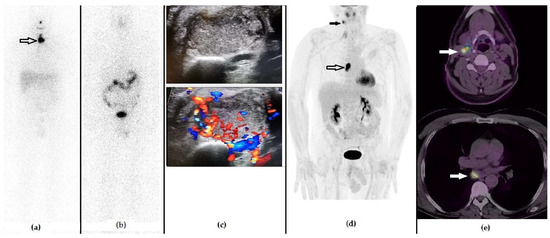

Figure 5. A 56-year-old male that previously underwent a thyroidectomy plus CND and 1 cycle of RAI due to Hürthle cell carcinoma (pT1b N1b). The first panel represents the post-RAI 131I-WBS showing the residual iodine-avid tissue in the anterior cervical region ((a), black arrow). Fifteen months after RAI, he presented with a slightly increased value of stimulated Tg serum level (i.e., 3.5 ng/mL), negative 131I-WBS (b) and neck US showing hypervascularized laterocervical node suspected of metastasis. (c) 18F-FDG PET/CT demonstrated a highly increased tracer incorporation in the suspected right laterocervical node, ((d) black arrow) also revealing metastases to the mediastinal nodes ((d), black bordered arrow), as evident in the whole body (d) and in the fused PET/CT axial images (e). The patient underwent surgery, followed by a further cycle of RAI.